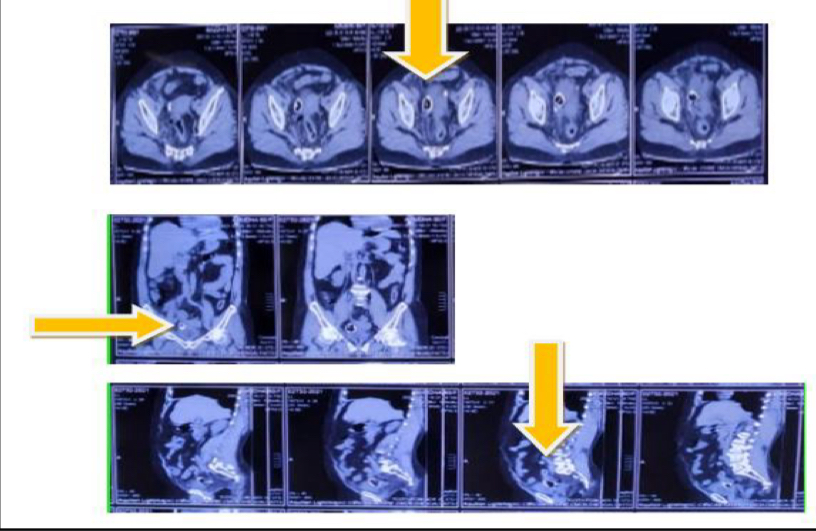

Figure 3. Инородное тело повышенной плотности (стрелка), видимое на аксиальном, коронарном и сагиттальном срезах компьютерной томографии.